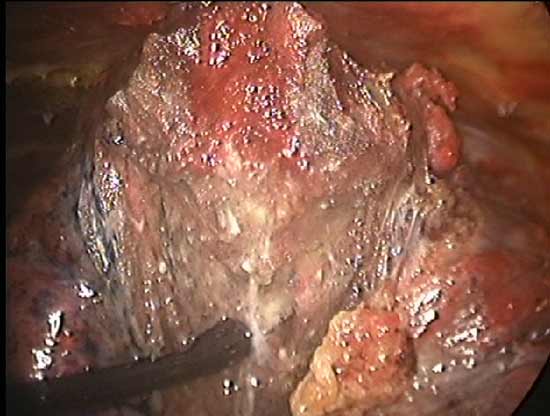

The TissueLink device does not perforate or cut into tissue (in contrast to conventional electrocautery). Instead, the surface of the tissue is painted with the device, which first coagulates and then shrinks the lung tissue (Figure 3). The surgeon then divides the coagulated tissue with scissors (Figure 4). Compared with conventional electrocautery, the TissueLink device usually leaves the resection bed more hemostatic and pneumostatic.